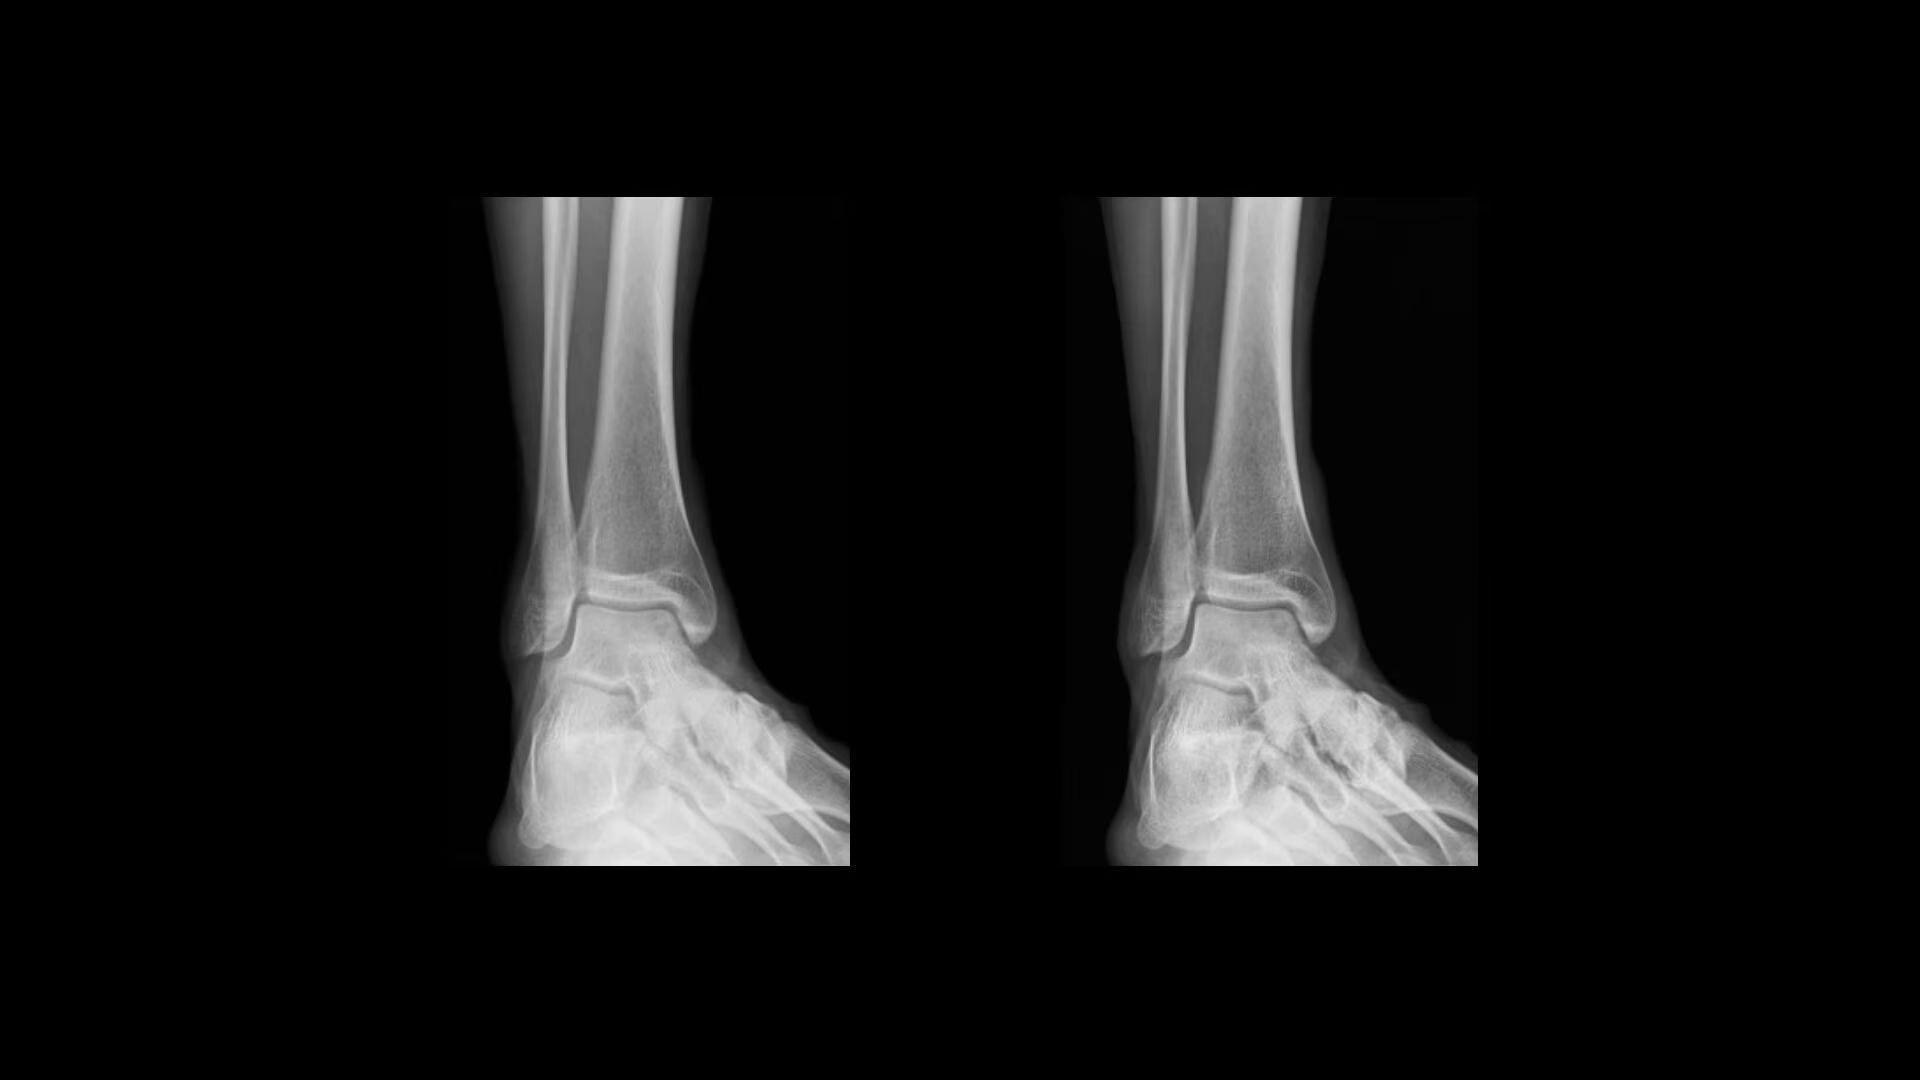

Clarity

Improve visualization and detail

Local Contrast Enhancement (LCE) increases local contrast in both pediatric and adult chest X-ray images for better visualization of the lungs, heart, and spine regions. It is also available for ankle joint (AP), foot (AP), and patella (tangential)*, and has three levels of enhancement (low, medium and high).

web-helix-feature-hero-st-en